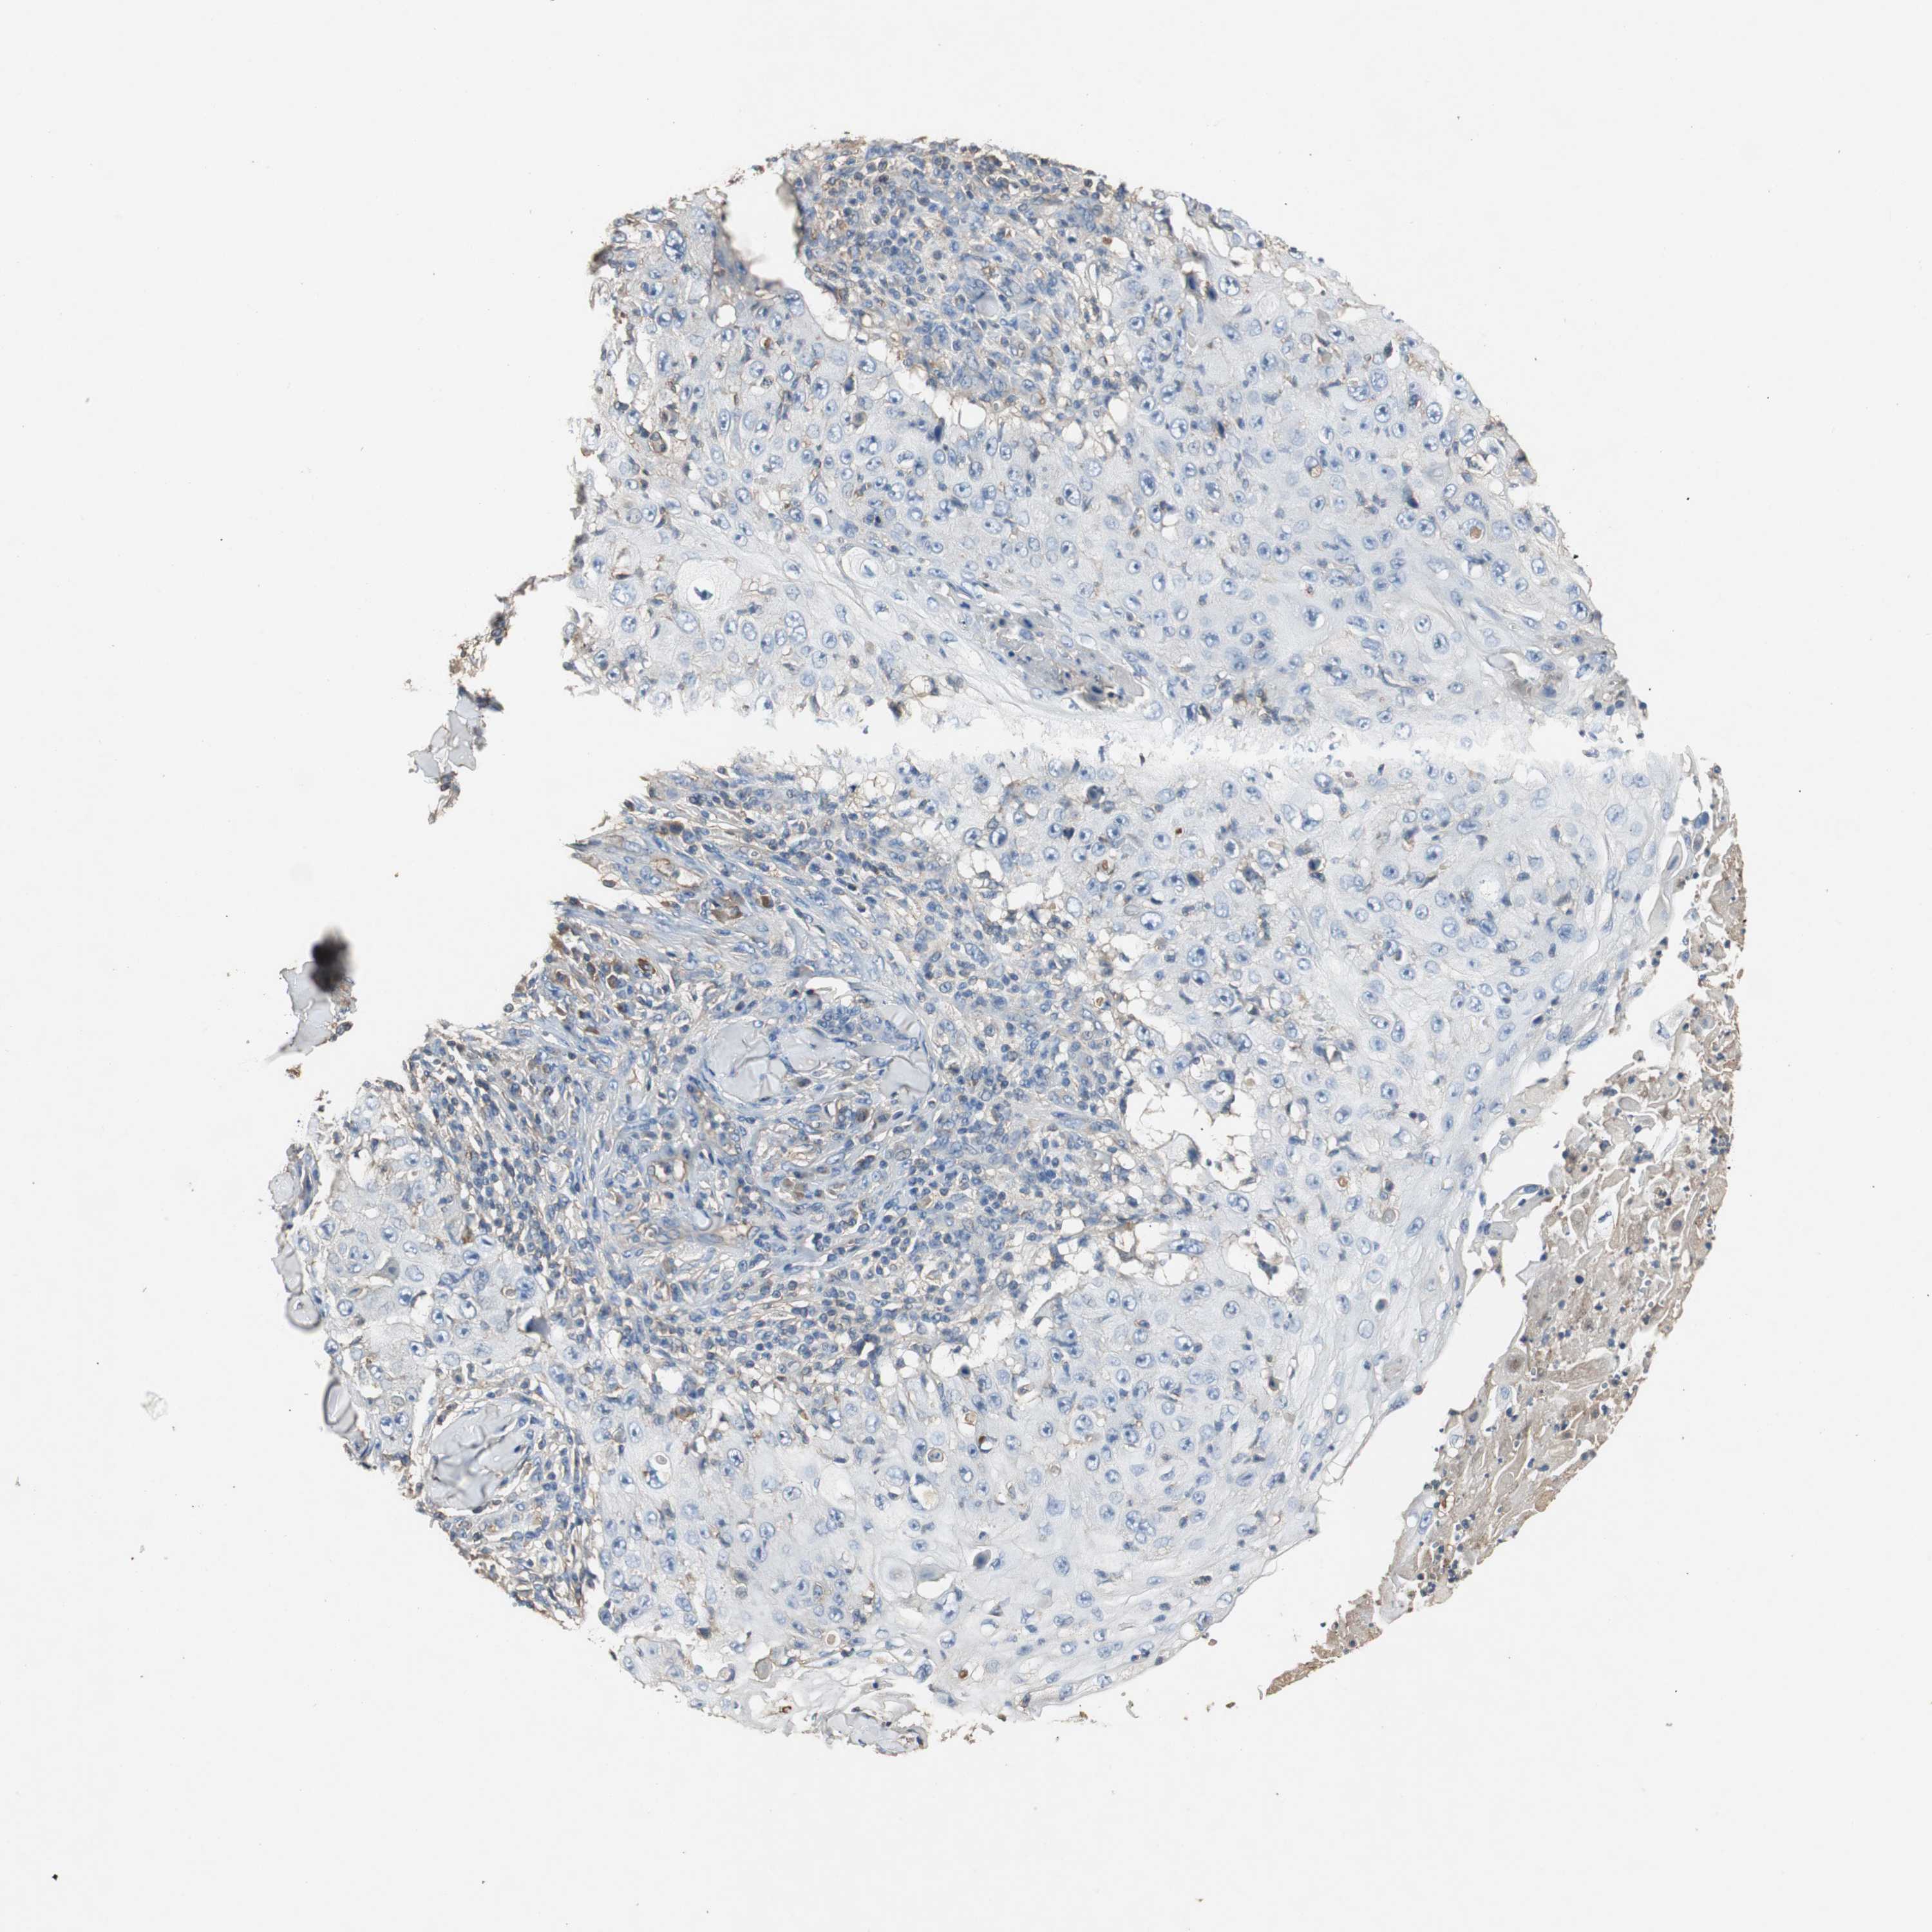

SKIN CANCER - Protein expressioni

A mouse-over function shows sample information and annotation data. Click on an image to view it in a full screen mode. Samples can be filtered based on level of antibody staining by selecting one or several of the following categories: high, medium, low and not detected. The assay and annotation is described here.

Antibody stainingi

Antibody staining in the annotated cell types in the current human tissue is reported as not detected, low, medium, or high, based on conventional immunohistochemistry profiling in selected tissues. This score is based on the combination of the staining intensity and fraction of stained cells.

Each image is clickable and will lead to virtual microscopy that enables deeper exploration of all samples and also displays staining intensity scores, fraction scores and subcellular localization as well as patient and tissue information for each sample.

Antibody CAB026150

Squamous cell carcinoma, NOS

Basal cell carcinoma

Squamous cell carcinoma, metastatic, NOS